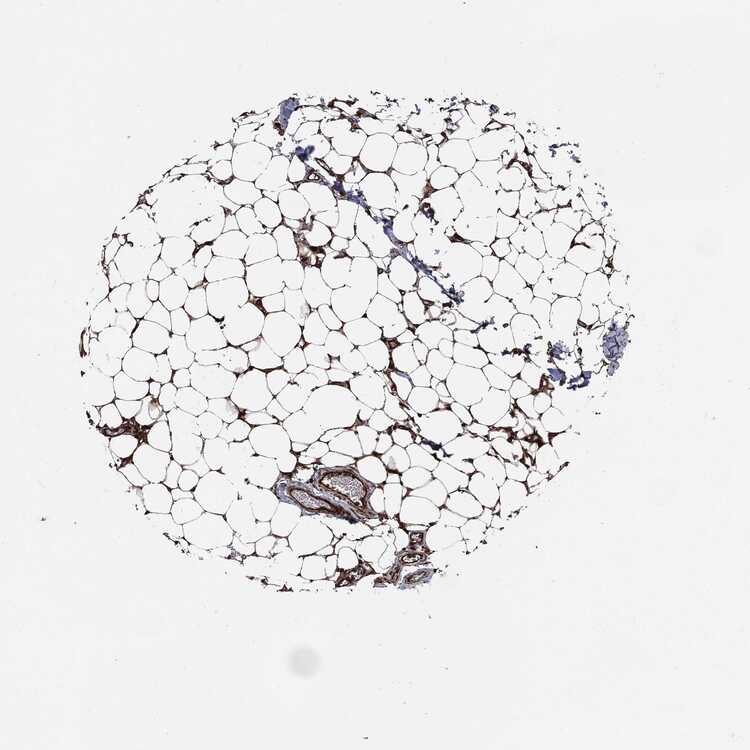

TISSUE PRIMARY DATA SOFT TISSUE Show tissue menu

SOFT TISSUE - Expression summary

SOFT TISSUE 1 - Antibody stainingi

Antibody staining in the annotated cell types in the current human tissue is reported as not detected, low, medium, or high, based on conventional immunohistochemistry profiling in selected tissues. This score is based on the combination of the staining intensity and fraction of stained cells.

Each image is clickable and will lead to virtual microscopy that enables deeper exploration of all samples and also displays staining intensity scores, fraction scores and subcellular localization as well as patient and tissue information for each sample.

Antibody HPA055380Antibody CAB045980Antibody CAB080338

Chondrocytes Not detectedNot detectedHigh

Fibroblasts Not detectedNot detectedHigh

Peripheral nerve -MediumLow